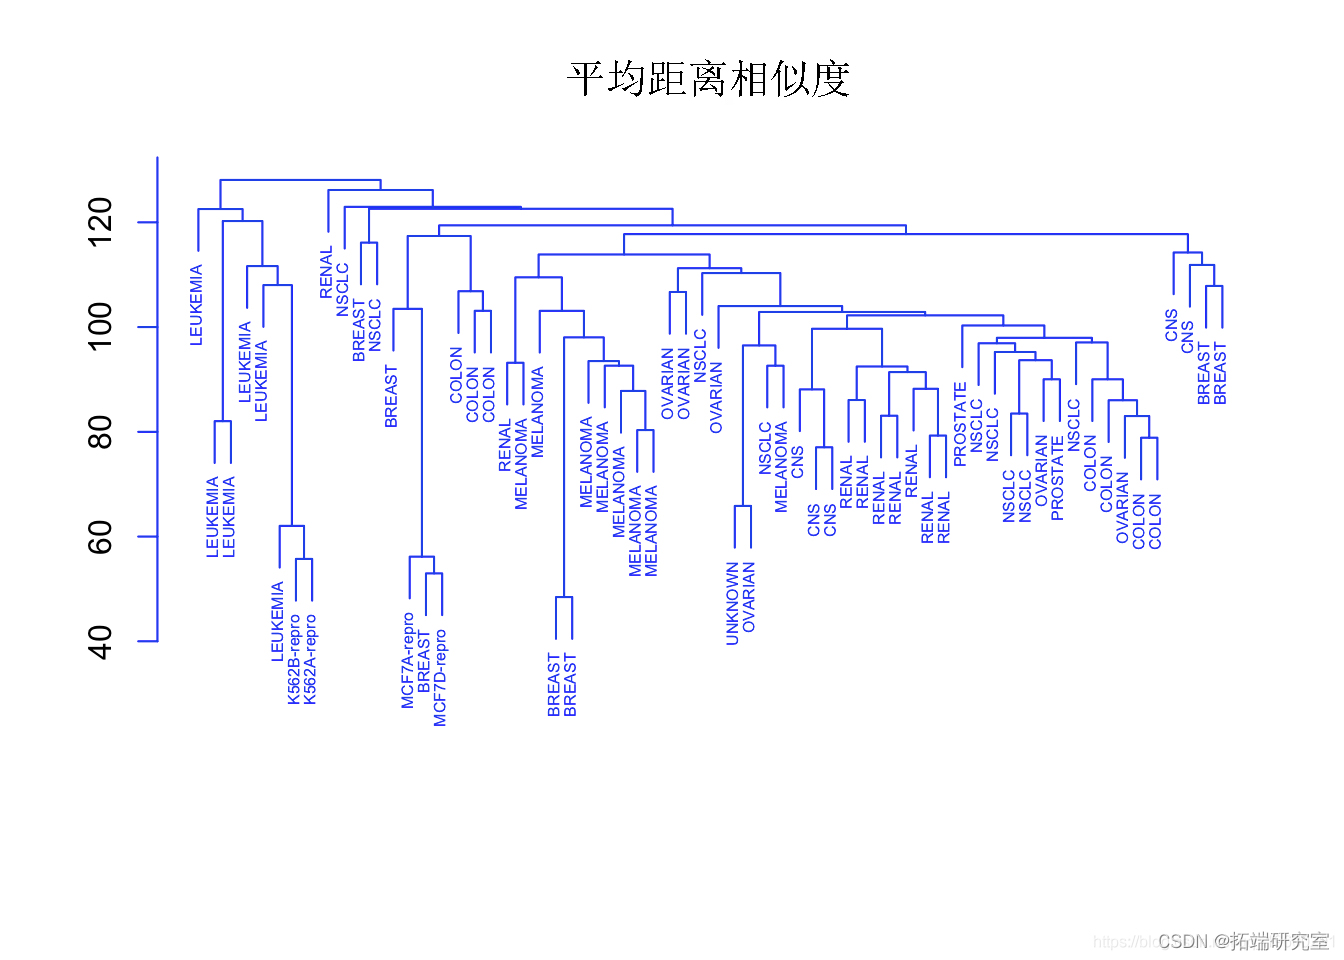

scale # 标准化变量(均值零和标准差一)。全链接、平均链接和单链接之间的比较。

plot(hclust,cex=".5",col="blue") #使用平均链接对观察进行层次聚类。

观察结果

另一方面,全链接和平均链接往往会产生更加平衡和有吸引力的聚类。

由于这个原因,全链接和平均链接比单链接层次聚类更受欢迎。单一癌症类型中的细胞系确实倾向于聚在一起,尽管聚类并不完美。